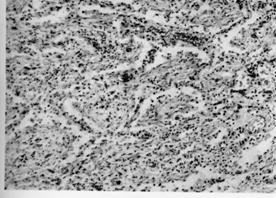

4.痰塗片或培養和組織學檢查發現麴黴菌絲或孢子。

麴黴球其他輔助檢查:X線上麴黴球表現為肺空洞或胸膜腔內圓形緻密陰影,其邊緣有透光暈影。若空腔較大,尚可見球形陰影有蒂與洞壁相連,形如鐘擺,球形陰影可隨體位變化而改變形態。如果空洞較小,球形病灶填充了大部分空腔,其暈影很小,僅呈一狹長的半月形透亮帶。有學者曾在2例X線平片、體層片和支氣管造影片均無陽性發現的隱源性大咯血患者套用支氣管動脈造影定位後行手術治療,病理髮現1cm左右的細小支氣管囊腫繼發麴黴球。胸部CT檢查特別是高分辨CT的套用為發現細小麴黴球和鑑別診斷提供了有用技術。